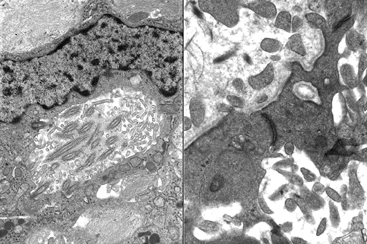

Question 33: A three year old boy had a cerebellopontine angle tumor with the ultrastructural features illustrated below.

Incorrect. The key EM findings are microvilli and dense junction, consistent with ependymoma.

Correct. The key EM findings are microvilli and dense junction, consistent with ependymoma.